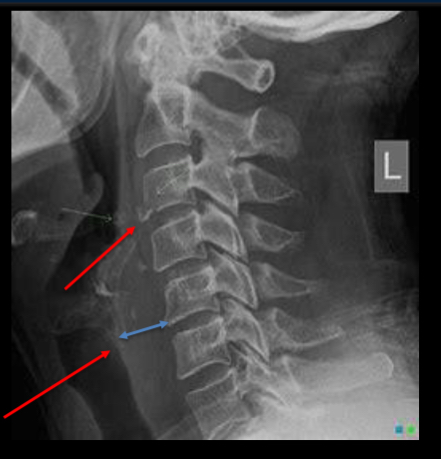

describe this radiograph

Anterior soft tissue measuring more

than 20mm at the level of C6.

• Indicates possible trauma.

• Patient has a tear-drop fracture of the

vertebral body of C3